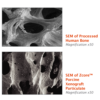

• Interconnecting macroscopic and microscopic porous structure supports the formation and ingrowth of new bone

• 88% to 95% Void Space: hyper-porosity of porcine cancellous matrix and intra-particle space facilitated by rough particle morphology reduce bulk density of the graft, allowing greater empty space for new bone growth

Zcore™ is an osteoconductive, porous, anorganic bone mineral with a carbonate apatite structure derived from porcine cancellous bone. Proprietary processing steps preserve both interconnecting macroscopic and microscopic porous structures of Zcore™ that helps support the formation and in-growth of new bone.